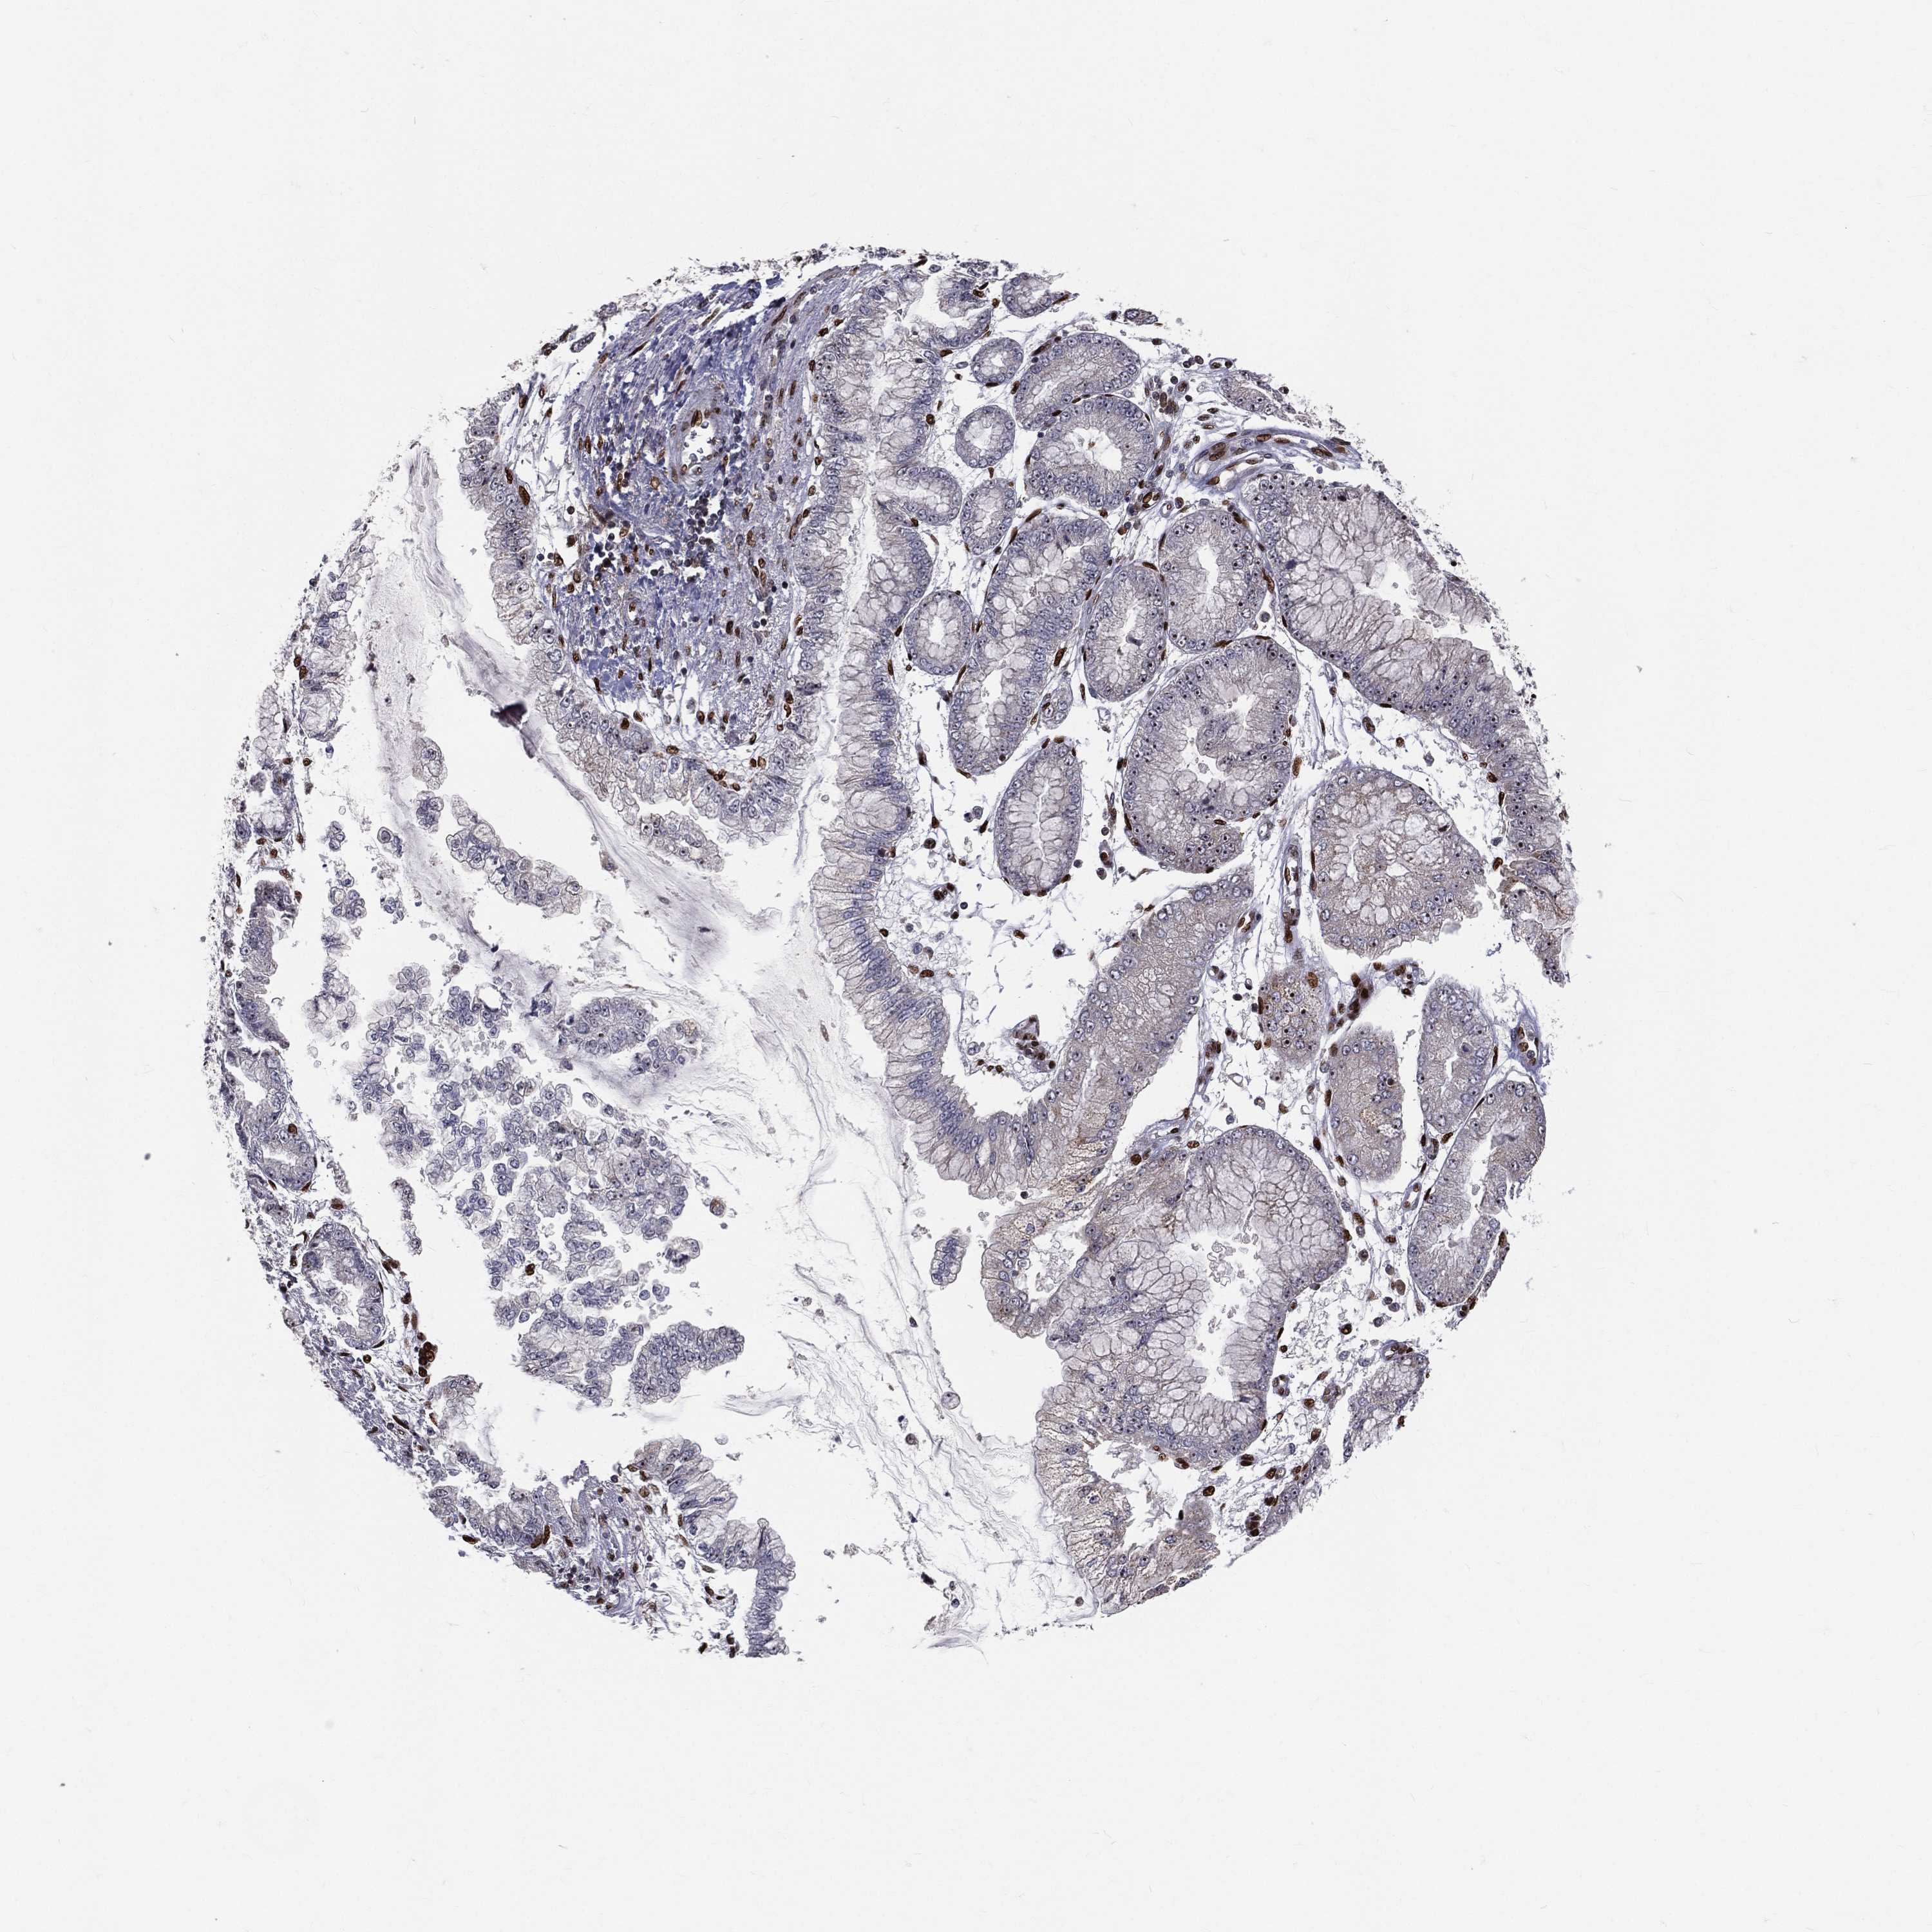

STOMACH CANCER - Protein expressioni

A mouse-over function shows sample information and annotation data. Click on an image to view it in a full screen mode. Samples can be filtered based on level of antibody staining by selecting one or several of the following categories: high, medium, low and not detected. The assay and annotation is described here.

Antibody stainingi

Antibody staining in the annotated cell types in the current human tissue is reported as not detected, low, medium, or high, based on conventional immunohistochemistry profiling in selected tissues. This score is based on the combination of the staining intensity and fraction of stained cells.

Each image is clickable and will lead to virtual microscopy that enables deeper exploration of all samples and also displays staining intensity scores, fraction scores and subcellular localization as well as patient and tissue information for each sample.

Antibody HPA027524

Antibody CAB058686

Antibody CAB079943

Staining

High

Medium

Low

Not detected

Intensity

Strong

Moderate

Weak

Negative

Quantity

>75%

75%-25%

<25%

None

Location

Nuclear

Cytoplasmic/membranous

Cytoplasmic/membranous,nuclear

Adenocarcinoma, NOS

Adenocarcinoma, High grade